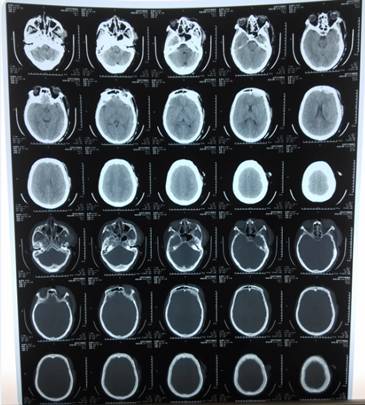

经检查,患者车祸致脑挫裂伤,硬膜外血肿。时间紧迫,吴老师立即指挥现场急救人员:”直接送往手术室,通知手术室,准备急诊开颅手术!!!